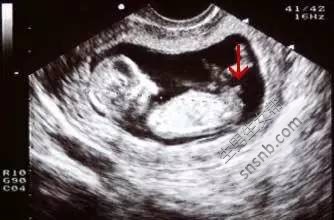

一、看孕囊大小

1、7W+1D的BC数据: 胎囊2.9*1.9 生的是男孩;

2、9W+4D的BC数据: 宫内见46.6*30.2mm孕囊 双胞胎都是女孩;

3、60天的BC数据: 孕囊大小是3.6*1.6MM 生下的是帅哥;

4、5W+6D。孕囊:25mm*11mm 男孩;

5、数据:胚囊:23x17x16 生下的是可爱的女宝宝;

6、46天BC数据:孕囊:20*17*17 女孩;

7、7w+1D的BC结果:32*20mm妊娠囊 女孩;

8、8周时是1.6×1.7 生下的是千金

9、8周的时候是41*28MM 生下的也是女宝宝;

10、8周多是的BC,胎囊是19MM*10MM 后来BC照出来也是男宝宝;

11、胎囊:35mmX34mmX28mm 是女孩;

12、孕囊大小:(长)18MM X(宽)16MM X (厚)8MM 是千金。